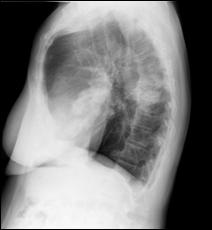

4.5. Radiografia osoasa 4. Radiografia toraco-pulmonara

Figura 44. Metastaza in articulatia coxo-femurala

dreapta Figura 45. Metastaze pulmonare multiple dintr-un carcinom vezical

Figura 4 Radiografie toraco-pulmonara cu metastaze pulmonare multiple

dintr-un carcinom vezical infiltrativ

Figura 47. Radiografie toraco-pulmonara cu metastaze pulmonare multiple dintr-un carcinom vezical infiltrativ.